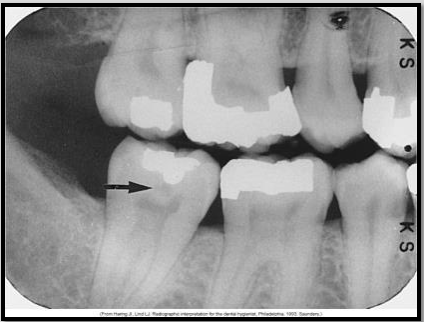

Describe Recurrent caries

AKA Secondary caries

Evident adjacent to pre-existing restoration due to inadequate cavity prep, defective margins, or incomplete removal of caries prior to placing restoration

appears as radiolucent area just beneath restoration on radiograph.